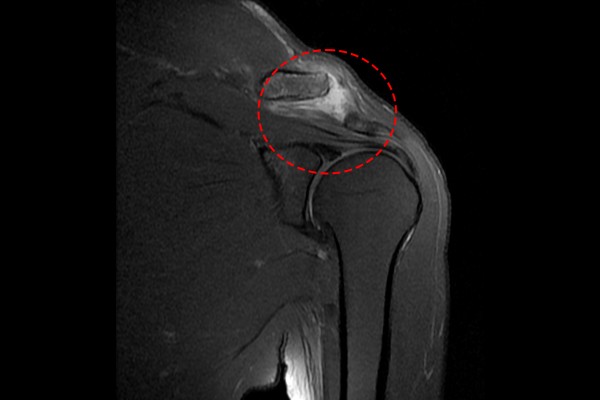

탈구뿐만 아니라 인대나 힘줄 등, 연부조직의 손상여부를 자세히 파악하기 위해 추가적으로 촬영한 MRI 검사에서 견봉-쇄골인대가 파열되어, 견봉-쇄골 관절이 탈구되어 있음을 확인하여, 좌측 어깨 견봉-쇄골 인대파열 및 오구-쇄골인대 파열로 인한 견봉-쇄골관절 탈구 및 오구-쇄골관절 탈구(A-C(acromio-clavicular) & C-C(coraco-clavicular)ligament rupture & joint subluxation shoulder Lt.)를 진단하였습니다.(증상이 심한 경우에는 쇄골이 위로 튀어나와 만져지기도 합니다.)